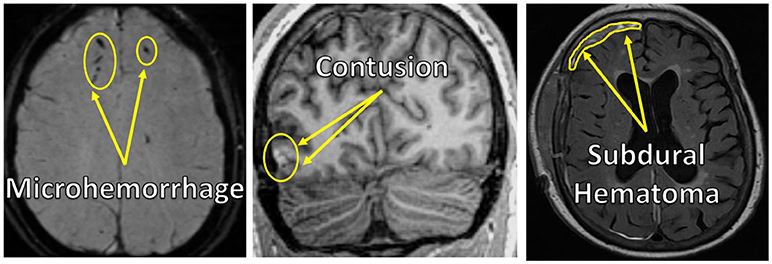

Efter en traumatisk hjerneskade er der forskellige former for skader på hjernen, som billeddannende teknologier kan hjælpe lægerne med at se. Gode billeddannelsesmetoder, der lader lægerne se hele hjernen, er meget vigtige for at finde ud af, præcis hvordan hjernen er blevet skadet. De mest almindelige skader er små blødninger i hjernen, kaldet mikroblødninger eller mikroblødninger (se figur 3), hvilket betyder en lille (“mikro”) udstrømning af blod fra et revet blodkar (“blødning”). Hvis du får næseblod, er det også en form for mikroblødning i næsemembranen. Hjernen har brug for en kontinuerlig tilførsel af ilt fra blodet for at kunne udføre sine daglige funktioner. Ilten transporteres til hjernen via blodkar, som findes i mange forskellige størrelser, fra store arterier til bittesmå kapillærer. De mindre blodkar menes at være særligt sårbare over for hjerneskader, fordi de kan strækkes og presses sammen, når hjernen bliver skubbet rundt i kraniet under en skade. På en CT-scanning ser disse mikroblødninger anderledes ud end det omgivende hjernevæv og har en klar “signatur”, da blodet samler sig i området (se pilene, der peger på de mørke prikker i venstre side af figur 3). MR-scanning er en mere følsom måde at identificere disse mikroblødninger og andre typer af hjerneskade på [1], men MR tager længere tid end CT, så når der er tale om alvorlige traumer, bruges CT stadig oftere til at få et hurtigt billede af, hvad der foregår i hjernen. En anden styrke ved MR frem for CT er, at den kan bruges til at tage forskellige slags billeder, hvorimod CT kun tager én type billede. Med MR kan vi kontrollere molekylernes magnetiske excitationsegenskaber på måder, der ændrer kontrasten på de billeder, vi indsamler. Hvor én type MR-billede kan få blod til at fremstå lyst, kan en anden få det til at fremstå mørkt, og disse forskelle i kontrast hjælper radiologerne til med større sikkerhed at afgøre, om de ser noget unormalt i hjernen, f.eks. blod eller blå mærker i hjernevævet som følge af en skade.

En anden almindelig hjerneskade kaldes en kontusion (se pilene, der peger på den lyse plet nederst til venstre i midterpanelet i figur 3), som er et blåt mærke på hjernen på grund af et traume. Ligesom blå mærker, man får på armen eller benet efter et fald, omfatter en hjernekontusion ofte en samling af blødninger i et lokaliseret område. I modsætning til et blåt mærke på armen eller benet, som heler med tiden og ikke efterlader mærker efter skaden, kan hjernekontusioner og skaden på det omkringliggende hjernevæv være mere permanent. Ved at se ind i hjernen ved hjælp af CT- eller MR-scanning kan lægerne visualisere hjernekontusioner, hvilket hjælper lægerne med at afgøre, hvordan de bedst kan diagnosticere, behandle og pleje patienter med traumatisk hjerneskade.

Ud over mikroblødninger og kontusioner er der en række traumatiske hjerneskader, der opstår i det, der kaldes det “ekstra-aksiale rum”. Det ekstraaksiale rum er rummet mellem hjernens overflade og indersiden af kraniet. Der er forskellige rum i det ekstraaksiale rum, kaldet det subdurale (se pilene, der peger på det lyse bånd øverst til venstre i det højre panel i figur 3), epidurale eller subaraknoide ekstraaksiale rum. Disse rum består af forskellige lag mellem hjernen og kraniet, og de indeholder en række blodkar, som kan gå i stykker og forårsage en blodansamling, der kaldes et hæmatom. Hæmatomer opstår oftest ved mere alvorlige hovedskader, der sker med større kraft og acceleration.